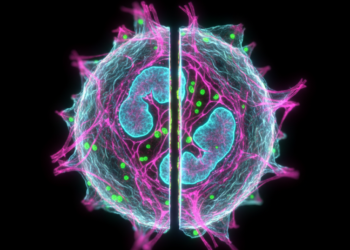

O estudo das células orais, como os queratinócitos, fibroblastos e células imunes, é fundamental para compreender várias condições de saúde bucal. Os cortes ópticos gerados pela microscopia confocal permitem que os cientistas investiguem a morfologia, organização e comportamento dessas células de maneira detalhada.

A capacidade de visualizar cortes múltiplos em 3D tem facilitado a identificação precoce de doenças bucais, como lesões neoplásicas e infecções. As imagens 3D celulares extraídas por meio da microscopia confocal proporcionam insights sobre como as células interagem entre si e podem servir como indicadores de progressão de doenças.

Após a captura de cortes ópticos pela microscopia confocal, as imagens podem ser processadas por softwares especializados para criar reconstruções tridimensionais. Este processo envolve a montagem de múltiplas camadas de imagens em um único modelo 3D, permitindo análises mais profundas e detalhadas.

Os softwares de reconstrução são projetados para combinar as imagens obtidas em diferentes planos focais, resultando em um modelo tridimensional. Com essa tecnologia, pesquisadores podem manipular a visualização, rotacionando e ampliando o modelo para examinar detalhes específicos. Isso é essencial para estudos em citologia e pode ser acessado em detalhes em nosso site sobre citologia.

Pesquisadores têm utilizado a microscopia confocal para identificar biomarcadores em tecidos orais que podem indicar doenças como câncer bucal. Estas observações ajudam não apenas na detecção precoce, mas também na avaliação da resposta ao tratamento.